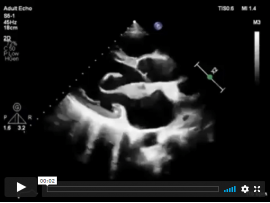

Lee masParasternal short axis view, Apical four chamber view “A4C”. By placing the probe in the 5th to 7th intercostal space with a pointer directed to the lateral side till u..

Lee masParasternal short axis view. Papillary muscle level. The importance is ; 1) can assess the LV function 2)Ischemia “RWMAs” 3)VSD 4)Flattened D-shaped septum in Pulmonary embolism 5)LV wall thickness 6)Papillary..